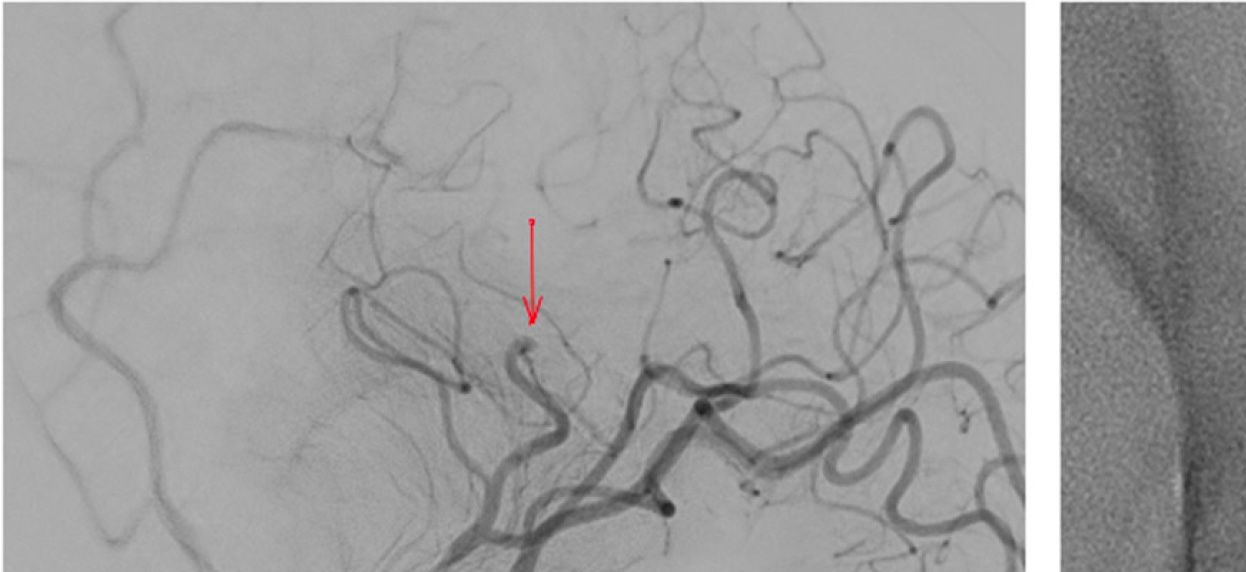

Challenging the limits of angioplasty: Comaneci device for distal vasospasm following subarachnoid hemorrhage

Long-term outcomes of temporary stent-assisted coil embolization for the treatment of intracranial aneurysms using Comaneci remodeling device

Jakub Onikijuk, MD et al.

Download PDF - 11/25 Challenging the limits of angioplasty: Comaneci device for distal vasospasm following subarachnoid hemorrhage Download PDF

- 5/22 Distal cerebral vasospasm treatment … Comaneci 10.1136/neurintsurg-2022-018699

- 7/20 Treatment of cerebral vasospasm … subarachnoid hemorrhage … PMID: 32722988 DOI: 10.1177/1591019920945554